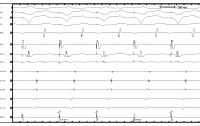

EKG bei Aufnahme

Abbildung 1: Elektrokardiogramm bei der Aufnahme auf die Intensivstation. Rhythmische Schmalkomplextachykardie, Frequenz 198/min, Rechtstyp, Fusion der P- und T-Wellen, QRS-Dauer 70 ms, R/S-Umschlag in V5, negative Ts in II, III, aVF, QT 270ms, QTc 402ms.